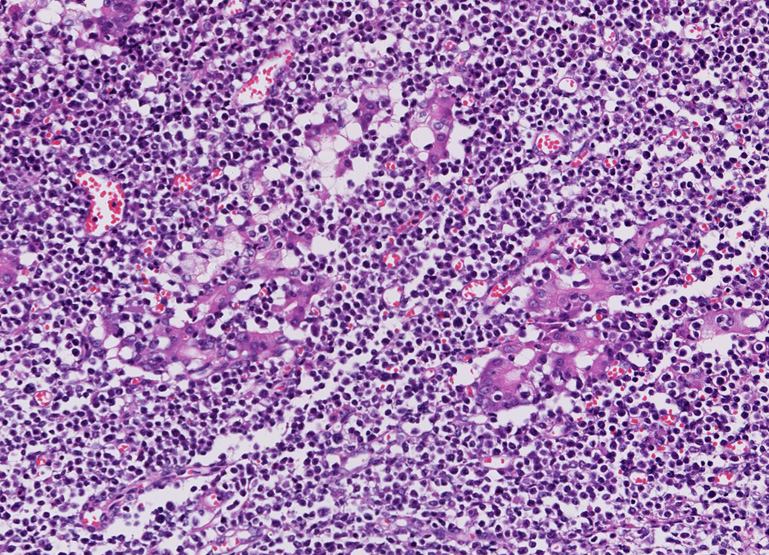

- 典型例はmarginal zoneのcentrocyte-like cellの増殖といわれるが非典型例も多い

- 分化してplasma cell様の形態をとる. Dutcher body(核内偽封入体)など異型所見あり。

| centrocyte-like cell | monocytoid cell | plasmacytoid |